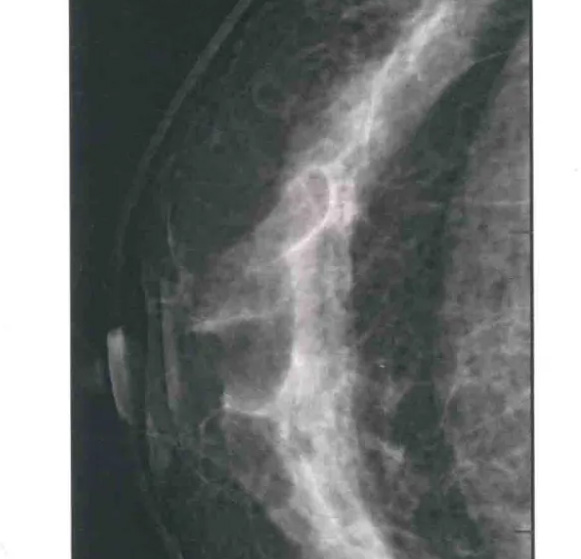

二、圖像顯示要求,含乳腺的基底部及內(nèi)外側(cè)乳腺組織,需要顯示胸肌前緣或胸壁。頭尾位與內(nèi)外斜位乳頭后線長度差≤1厘米;顯示實質(zhì)后的乳腺組織,乳頭位于切線位,乳腺組織重疊;雙側(cè)乳腺頭尾位照片相對放置,則兩側(cè)乳腺呈球形;影像密度和對比度良好,能顯示0.1毫米細(xì)小鈣化,清晰沒有偽影異物、運(yùn)動偽影和切割偽影等。